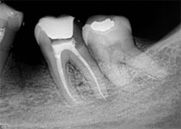

antes depois